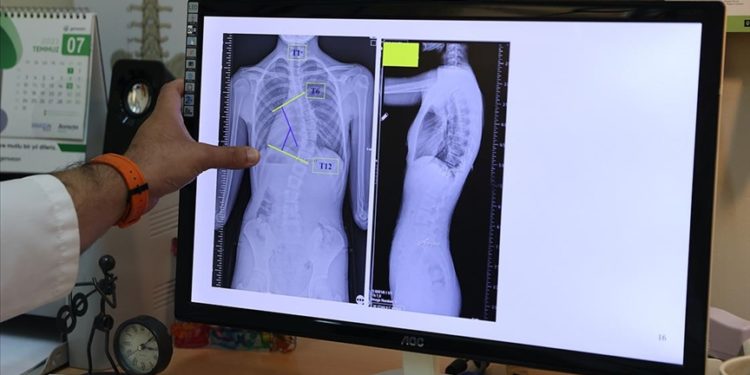

Doç. Dr. Coşkun, AA muhabirine, omurganın ön ve arka planında 10 dereceden fazla olan eğriliği skolyoz hastalığı olarak kabul ettiklerini belirtti.

Coşkun, skolyozun genellikle 10-19 yaş aralığında görüldüğüne işaret ederek, “Skolyoz, nedeni bilinmeyen bir hastalıktır. Ergenlik, adölesan idiopatik skolyozun en sık görülen yaş grubunu oluşturmakta. Şikayetler genelde omuzların bir tarafında yükseklik farkı olması, bir omuzun daha yukarıda yerleşmesi. Ayrıca hasta öne doğru eğildiğinde, hastada bir tarafında sırtında bir yükseklik, bir kamburluk bulgusu olması. Bu yükseltinin bir tarafta belirginleşme, diğer tarafta silinme, skolyozun ana bulgularındandır.” dedi.

“Skolyoz hastalığında tedavilerden biri gözlem tedavisidir. Gözlem skolyozda bir tedavidir. Biz gerçekten de 0 ila 20 derece arasındaki eğriliklere pek bir şey yapmayız. Bu çocukların gelişimini takip ederiz ve erişkin yaşa geldiğinde de bu tedaviyi sonlandırırız. Artık bu çocukların bir riski, hastalığın ilerlemesi açısından yoktur. 20 ila 40 derece arasında ise ya da 45 dereceye kadar biz çocuğun yaşı eğer uygunsa korse tedavisi uygularız. Korse tedavisi için çocuğun büyümesinin devam etmesi lazım. Kemik yaşı tamamlan, büyümesi tamamlanmış bir çocukta korse tedavisinin yeri yoktur. 45 dereceyi aşan eğriliklerde ise eğriliğin her sene ilerleyeceğini öngörerek cerrahi tedavi uygulamaktayız.”

Skolyozun özellikle kız çocuklarında daha sık görüldüğünün altını çizen Coşkun, ergenlik öncesi çekilecek bir omurga röntgeninin tedavide daha iyi yol alınmasını sağlayacağına işaret ederek, “Kız çocuklarında doğumsal kalça çıkığında olduğu gibi skolyoz yönünden tedbirli olmakta fayda var. Özellikle adet öncesi dönemde kızların en azından bir omurga röntgeninin çekilmesi, yine erkeklerde de ergenlik öncesi dönemde bir kez omurga röntgeninin çekilmesi olası bir skolyoz hastalığının tedavisine erken başlamak adına önemli. Çünkü tedaviye ne kadar erken başlarsak o kadar iyi sonuç alma ihtimalimiz yüksek.” ifadelerini kullandı.